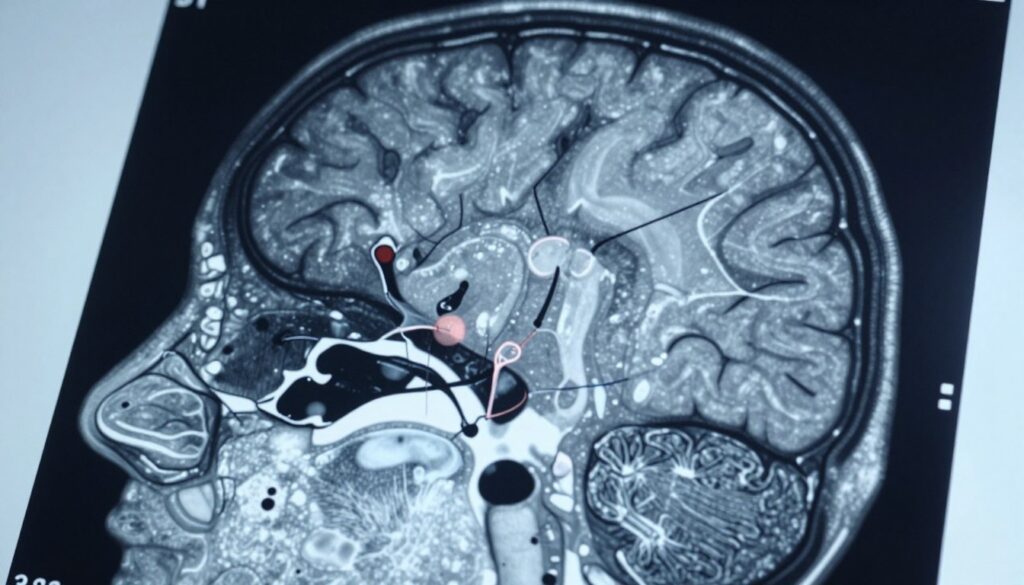

Rezonans magnetyczny pokazuje budowę mózgu i ewentualne zmiany anatomiczne. To najlepsza metoda obrazowania przy podejrzeniu ogniskowych napadów. Jednak sam obraz nie rejestruje aktywności elektrycznej, która powoduje napady.

Rezonans ukazuje strukturę mózgu i potrafi znaleźć zmiany, które tłumaczą napady. Typowe wykrywalne patologie to dysplazje korowe, guzy korowe, malformacje naczyniowe oraz zmiany poudarowe i pourazowe.

Rezonans magnetyczny identyfikuje też stwardnienie przyśrodkowego hipokampa i blizny pourazowe. Jednak badanie nie rejestruje bioelektrycznej aktywności mózgu, czyli samych wyładowań.

W napadach ogólnych często obraz pozostaje prawidłowy. Z kolei w napadach ogniskowych szansa znalezienia ogniska jest większa i może zmienić plan leczenia.

Jak czytać opis badania? „Brak zmian ogniskowych” nie eliminuje napadów. Opis „zmiany nieswoiste” wymaga korelacji z EEG i konsultacji w ośrodku specjalistycznym.